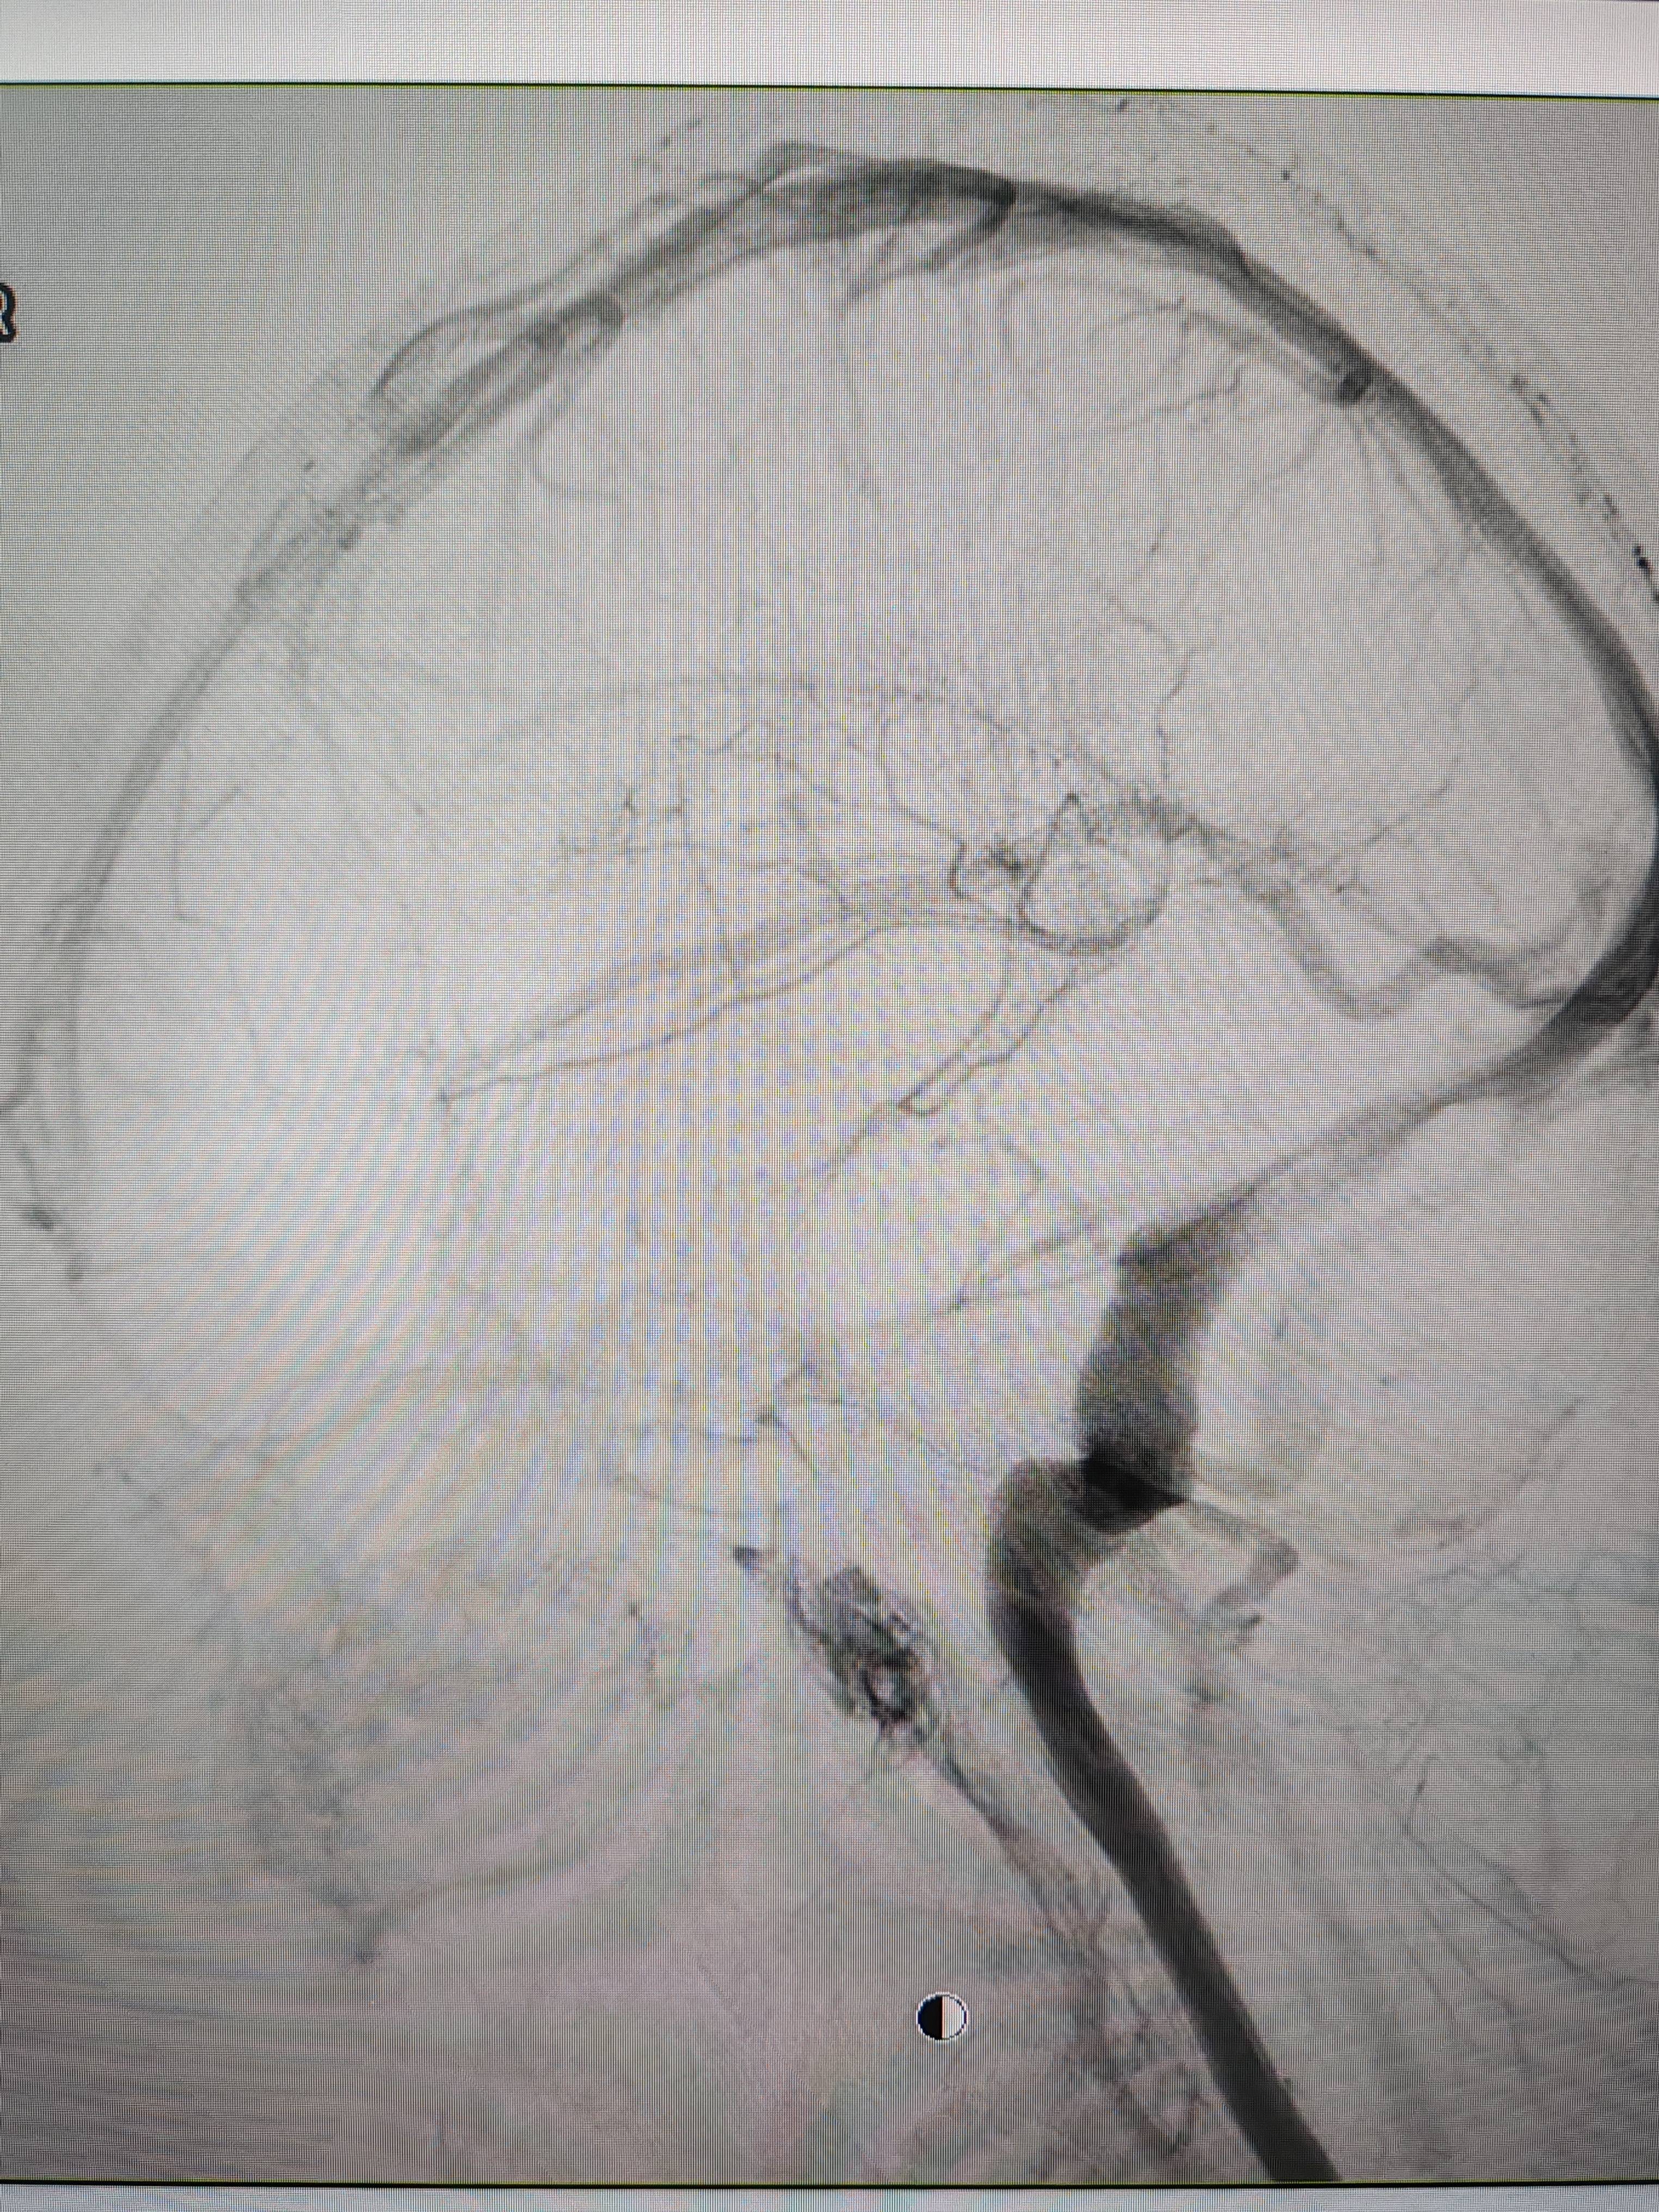

经过静脉窦支架置入手术治疗后,患者的静脉窦“堵点”被打通。 南方+ 欧阳少伟 拍摄

“从手术室出来,麻药清醒以后,我感觉整个世界都清静了,没想到效果这么立竿见影。”减轻病痛的赵女士,术后很是开心,次日就可下床自如活动,目前已康复出院。